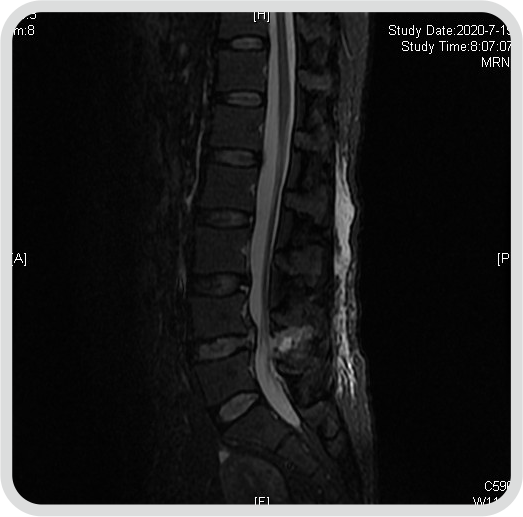

患者,黄某某,女,41岁,因左下肢疼痛伴麻木2年,加重半年入院;患者2年前无明显诱因出现左下肢疼痛,疼痛自臀部放射到小腿外侧,伴有足背部麻木感,活动后加重,于当地医院行CT检查示L4/5腰椎间盘突出,患者未予特殊治疗,近半年以来,感左下肢麻木疼痛加重,症状反复发作,行走后加重,影响日常生活,于院外的保守治疗无效。

查体: 腰椎生理曲度存在,腰椎屈伸活动稍受限,L4/5棘突间及 棘突旁压痛,伴左下肢放射痛,左侧足背部感觉减退,双下肢肌力正常,左路背伸肌力4级一,左下肢直腿抬高试验及加强试验阳性,双侧膝腿反射(+),双侧跟健反射(+),巴氏征(-),双下肢水梢毛细血管充盈良好。

图1:术前磁共振